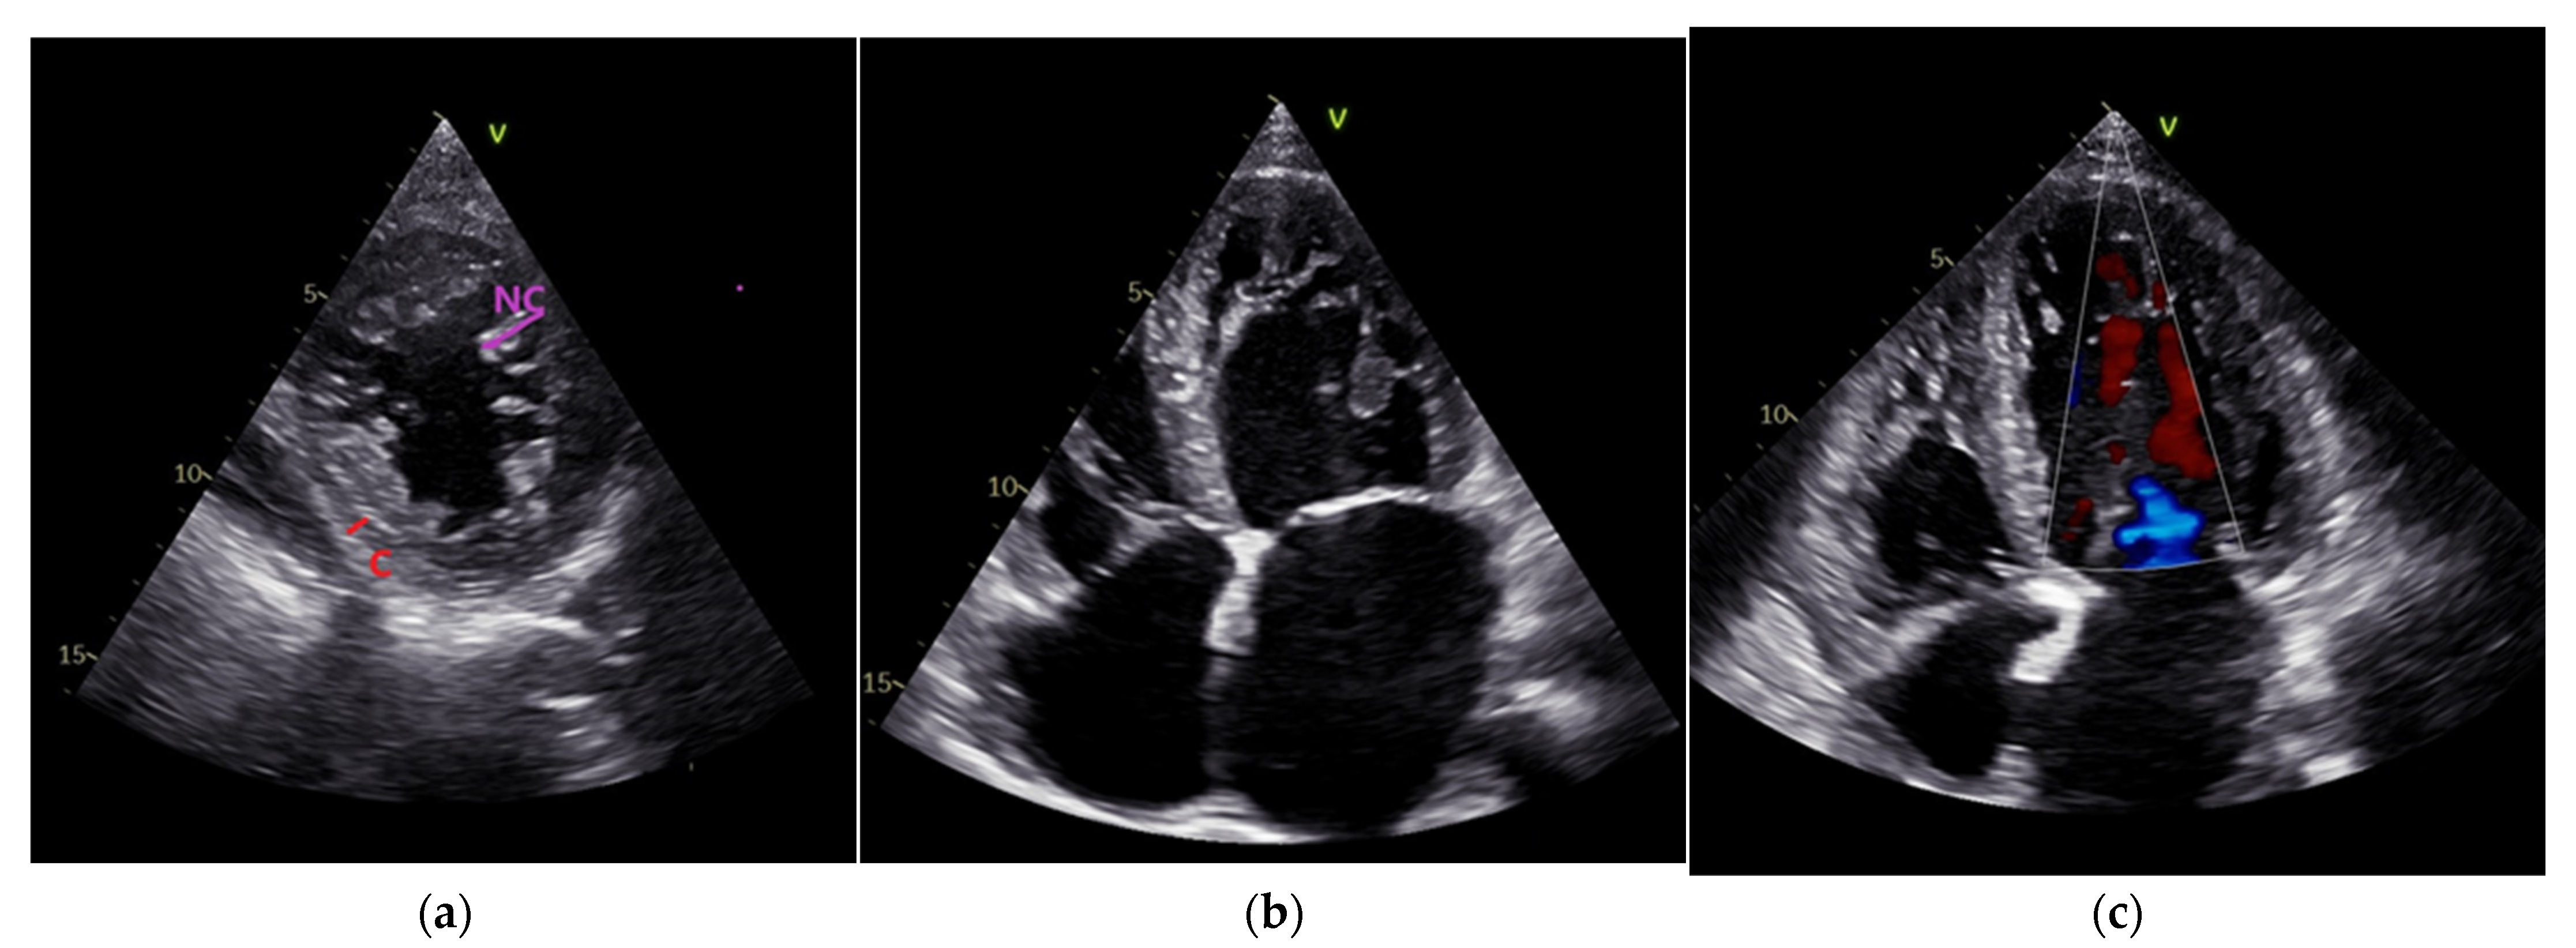

Transthoracic echocardiography (Figure 2, own archive of the last author), performed using VIVID E 95 (GE Vingmed Ultrasound AS, Horten, Norway), showed a moderately dilated LV with a morphologic image of a two-layered myocardium, which had trabeculations at the apex and in the mid-area of both the lateral anterior/inferior walls (Figure 2a,b). The ratio between the non-compacted/compacted myocardium at end systole in the short-axis perspective was 2.1. Color flow was present in the profound intertrabecular recesses (Figure 2c).

Figure 2.

(a) Transthoracic echocardiography. Parasternal short-axis view. Non-compacted–NC/Compacted-C ratio > 2; (b) Apical 4 chamber view. Trabeculations at the apex and lateral wall of the LV, dilated left atrium. (c) Transthoracic echocardiography. Color flow in the intertrabecular recesses.

The contraction of the LV was severely altered, and diffuse hypokinesia was present, which was accentuated at the trabeculated area level. The left atrium (LA) was severely dilated. A spontaneous contrast was present in the LA and LV. Moderate mitral regurgitation due to LV dilatation was present. Compared with the biplane Simpson method baseline, the LVEF was reduced, and the LV end systolic and end-diastolic volumes were increased (Table 1). A tissue Doppler revealed decreased velocities at the level of the septal and lateral annulus. Examination of the LV diastolic function revealed a restrictive filling pattern of mitral diastolic inflow with an E/e′ ratio = 15. The LVEF and global longitudinal strain were lower in the speckle tracking echocardiography results (35% and −9.2%). The characteristic of a decreased LV twist motion of 2.6 (determined using the difference between the peak rotation at the level of base and the apex in the short-axis view) for LVNC was found. The right ventricle had increased apical trabeculations but normal fractional area variations and a tricuspid annular plane systolic excursion (difficult to differentiate from the normal variant in the highly trabeculated right ventricle). The tricuspid regurgitation was medium, the inferior vena cava was dilated with diminished inspiratory collapse, and the systolic pressure in the pulmonary artery was 60 mmHg. A transthoracic echocardiographic examination was strongly suggestive of a LVNC CM with a dilation of the LV and a depressed ejection fraction. The morpho-functional phenotype for our patient according to the MOGE(S) system for cardiomyopathies is M LVNC-D, LVNC with LV dilatation, and dysfunction. Holter ECG (BTL-08 Holter H600, BTL Industries Ltd., Cleveland, United Kingdom) monitoring for 24 h showed ventricular premature beats at a percentage of 3%. Laboratory tests revealed an elevated NT-proBNP level (Table 2).